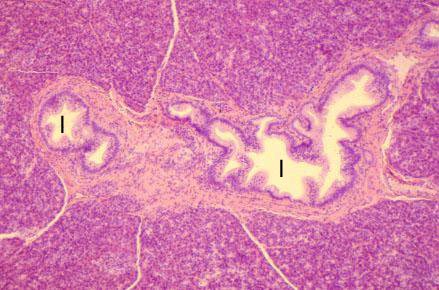

VIII-24 (4) Slide 68, Pancreas (H&E). Large ducts in connective tissue septum.